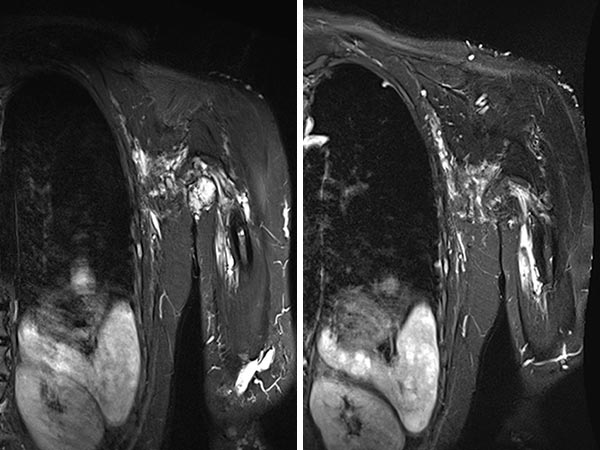

MRI (T2-weighted with fat suppression; axial plane) before (left) and after (right) bleomycin electrosclerotherapy. Only the locally treated parts of the lymphatic malformation (LM) have shrunk considerably, the remaining untreated parts are unchanged.MRI (T2-weighted with fat suppression; axial plane) before (left) and after (right) bleomycin electrosclerotherapy. Only the locally treated parts of the lymphatic malformation (LM) have shrunk considerably, the remaining untreated parts are unchanged.